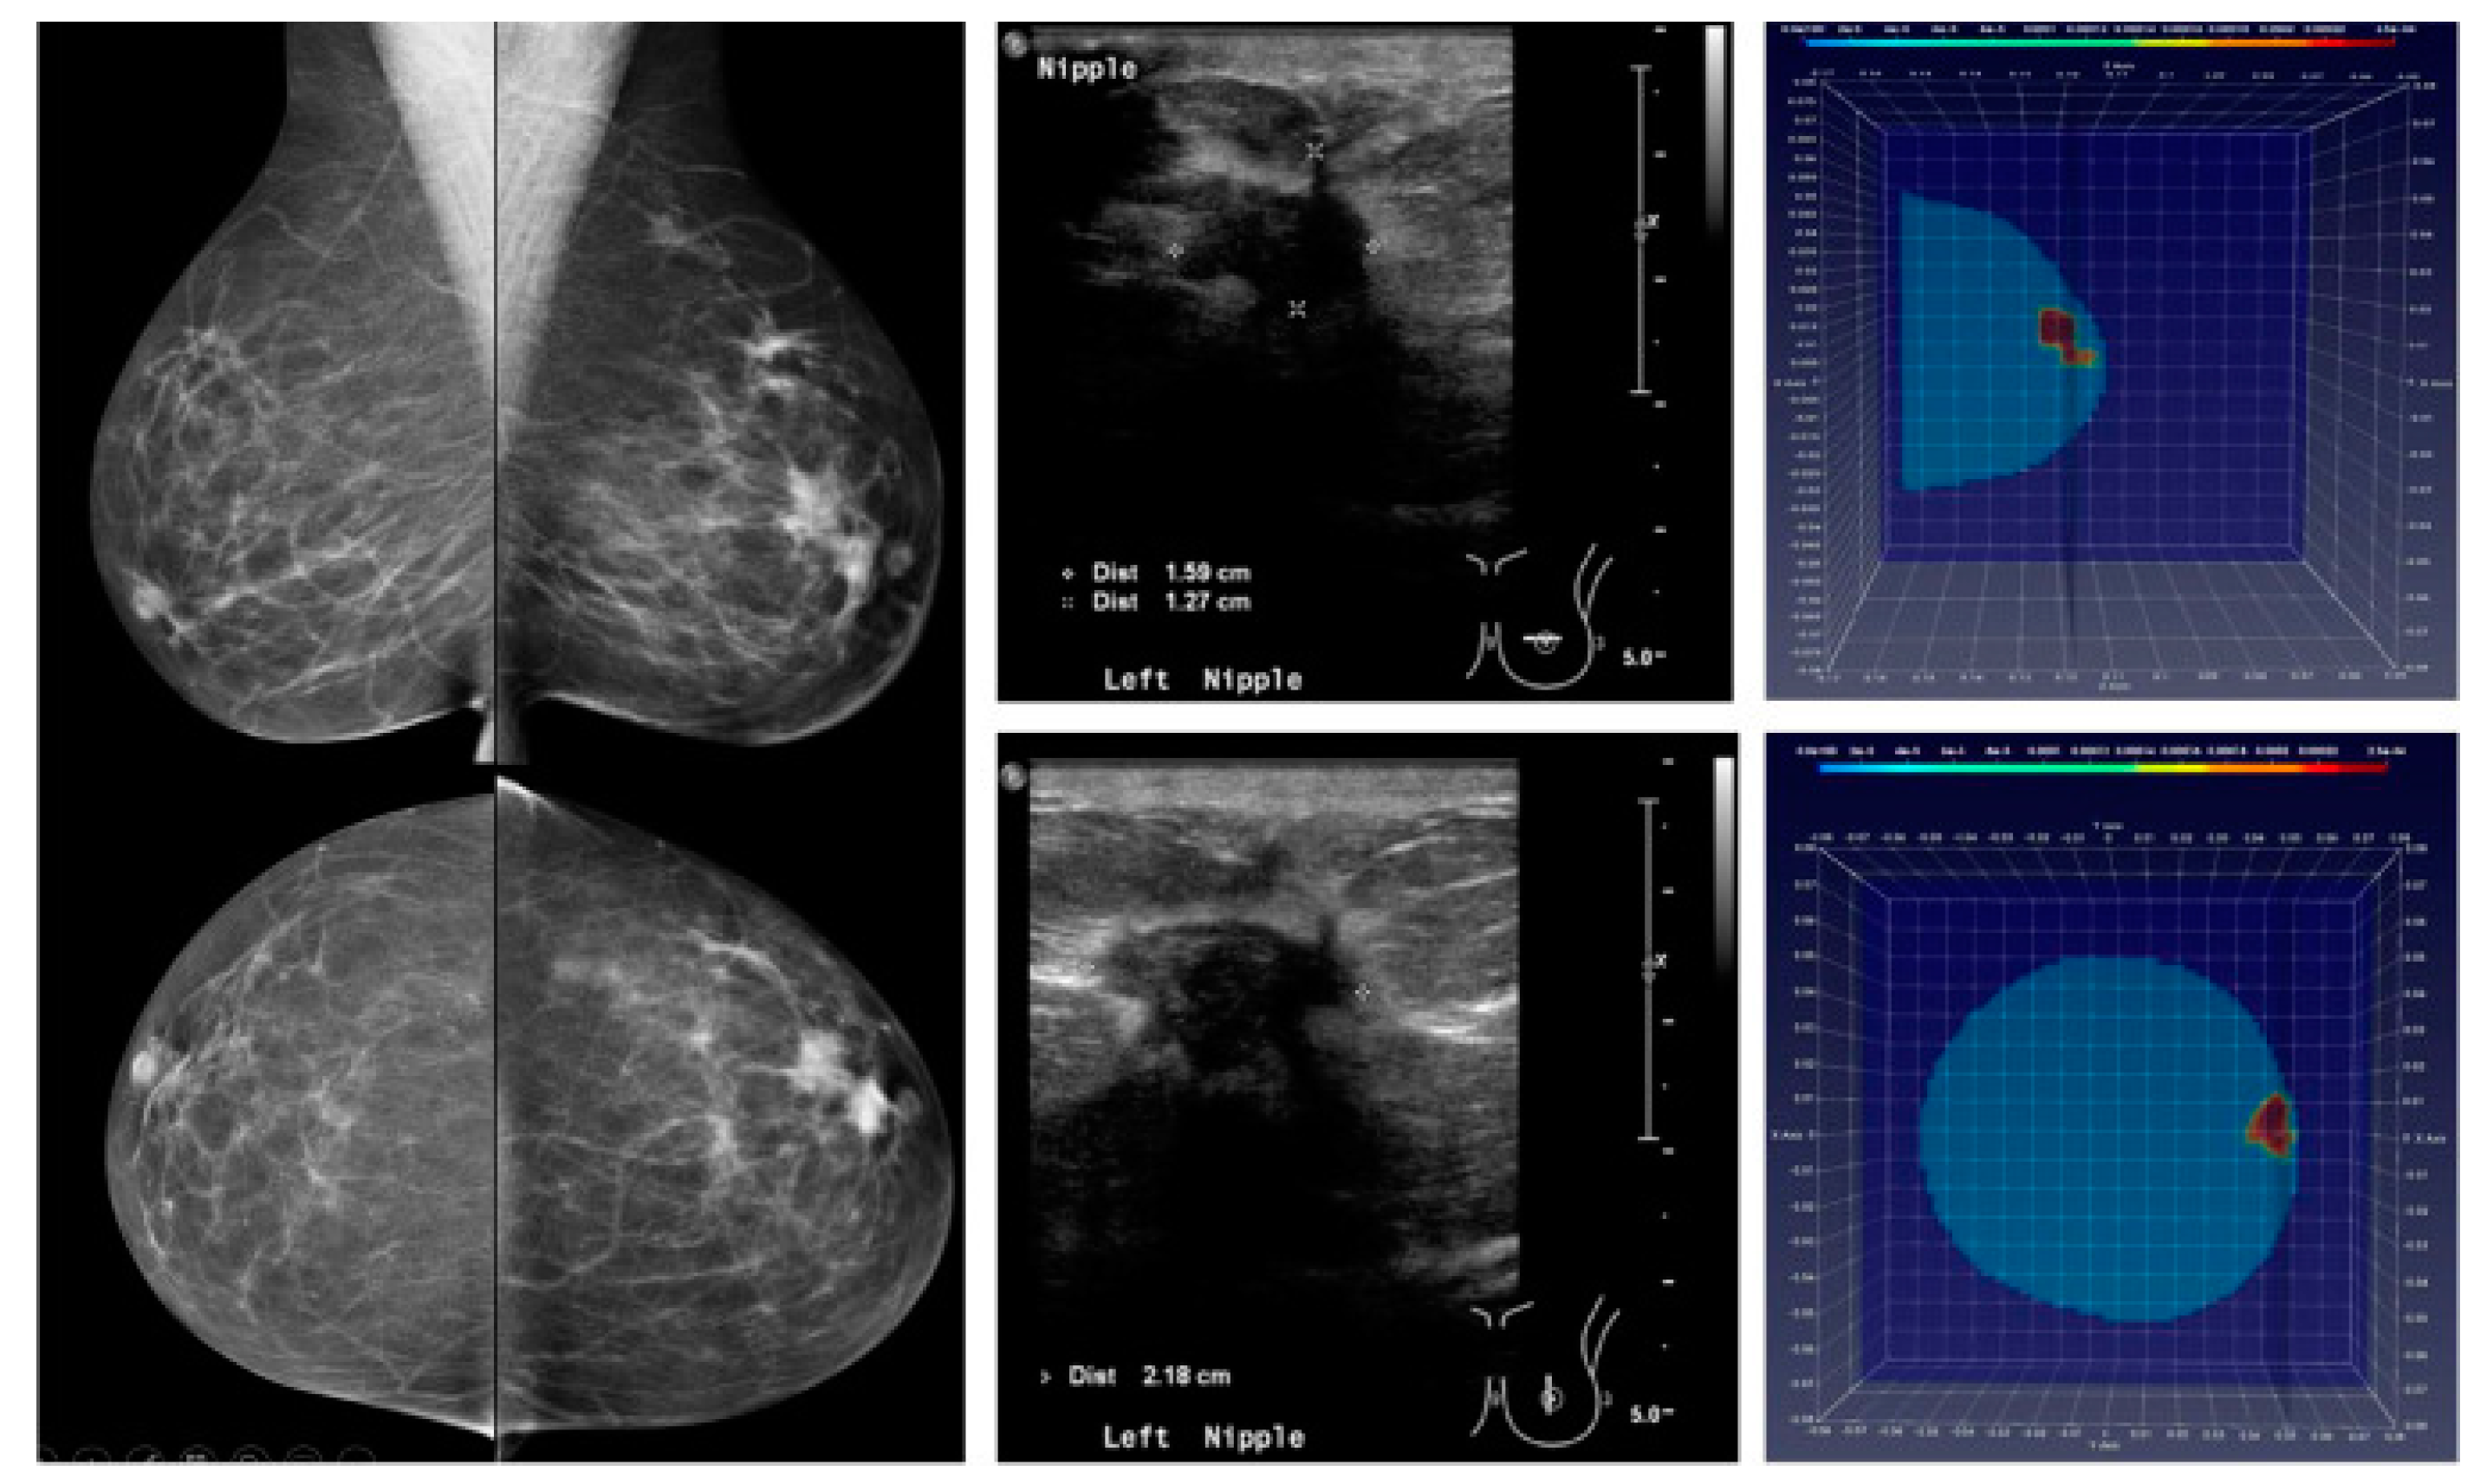

Furthermore, microwave imaging signals can be directly coupled to living breast tissue and then monitored for time-related changes during cancer treatment [15]. Figure 2 compares the imaging performance of regular X-ray mammography, ultrasonography and microwave tomographic imaging in breast cancer case. A visual inspection reveals clear and unequivocal detection and localization of the malignant lesion within the breast volume.

Figure 2. Mammography (left), ultrasonography (central panel) and MTI of a breast cancer patient. Reproduced from [16].